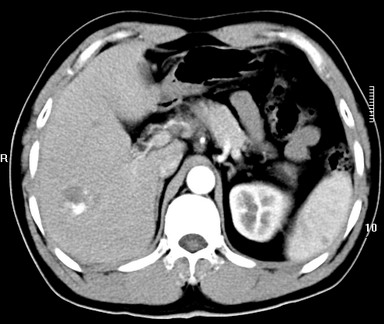

标题: CT19720:肝右叶血管瘤。肝左叶内侧段病灶考虑什么? [打印本页]

标题: CT19720:肝右叶血管瘤。肝左叶内侧段病灶考虑什么?

男,48岁,肝区不适月余,伴隐痛。

支持右叶血管瘤,左叶病灶考虑肝腺瘤。

1)不排除肝左叶肝癌。2)肝右叶血管瘤。

肝左叶炎性病变,肝癌待排。2)肝右叶血管瘤。

1.肝右叶血管瘤;2.肝左叶炎性假瘤?肝癌?建议穿刺活检.

右叶病灶典型,左叶病变慢性炎块

1、肝右叶血管瘤(典型)。

2、肝左叶病灶,强化不明显,疑炎性假瘤,建议结合临床并密切随访。

1、肝左叶炎性病变,肝癌待排。

2、肝右叶血管瘤。

肝左叶脓肿,肝癌待排。2)肝右叶血管瘤